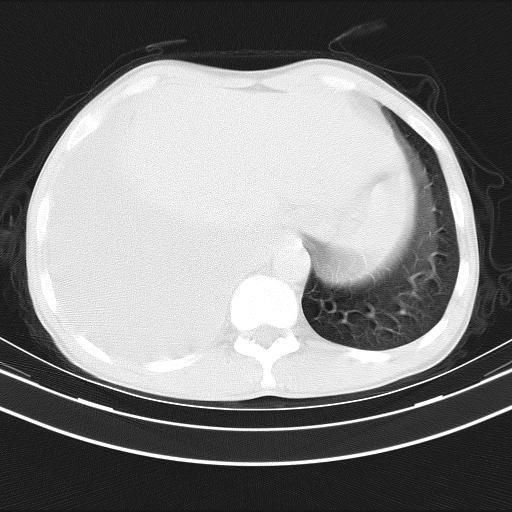

男性,44岁,结核病史多年。现胸闷气短,咳嗽,偶咳血。

1)两肺继发性肺结核伴空洞形成,左肺多发性结核球。2)右侧大量胸腔积液伴右肺部分膨胀不全。3)纵隔淋巴结肿大。

1,双肺多发结节 并空洞影改变, 左侧胸腔积液并部分包裹, 结合原病史首先考虑结核. 但也不除外其它.

2,左侧有一根肋骨陈旧性骨折? 建议追查 .

吉大一院胸水抽检结果:结核性胸水